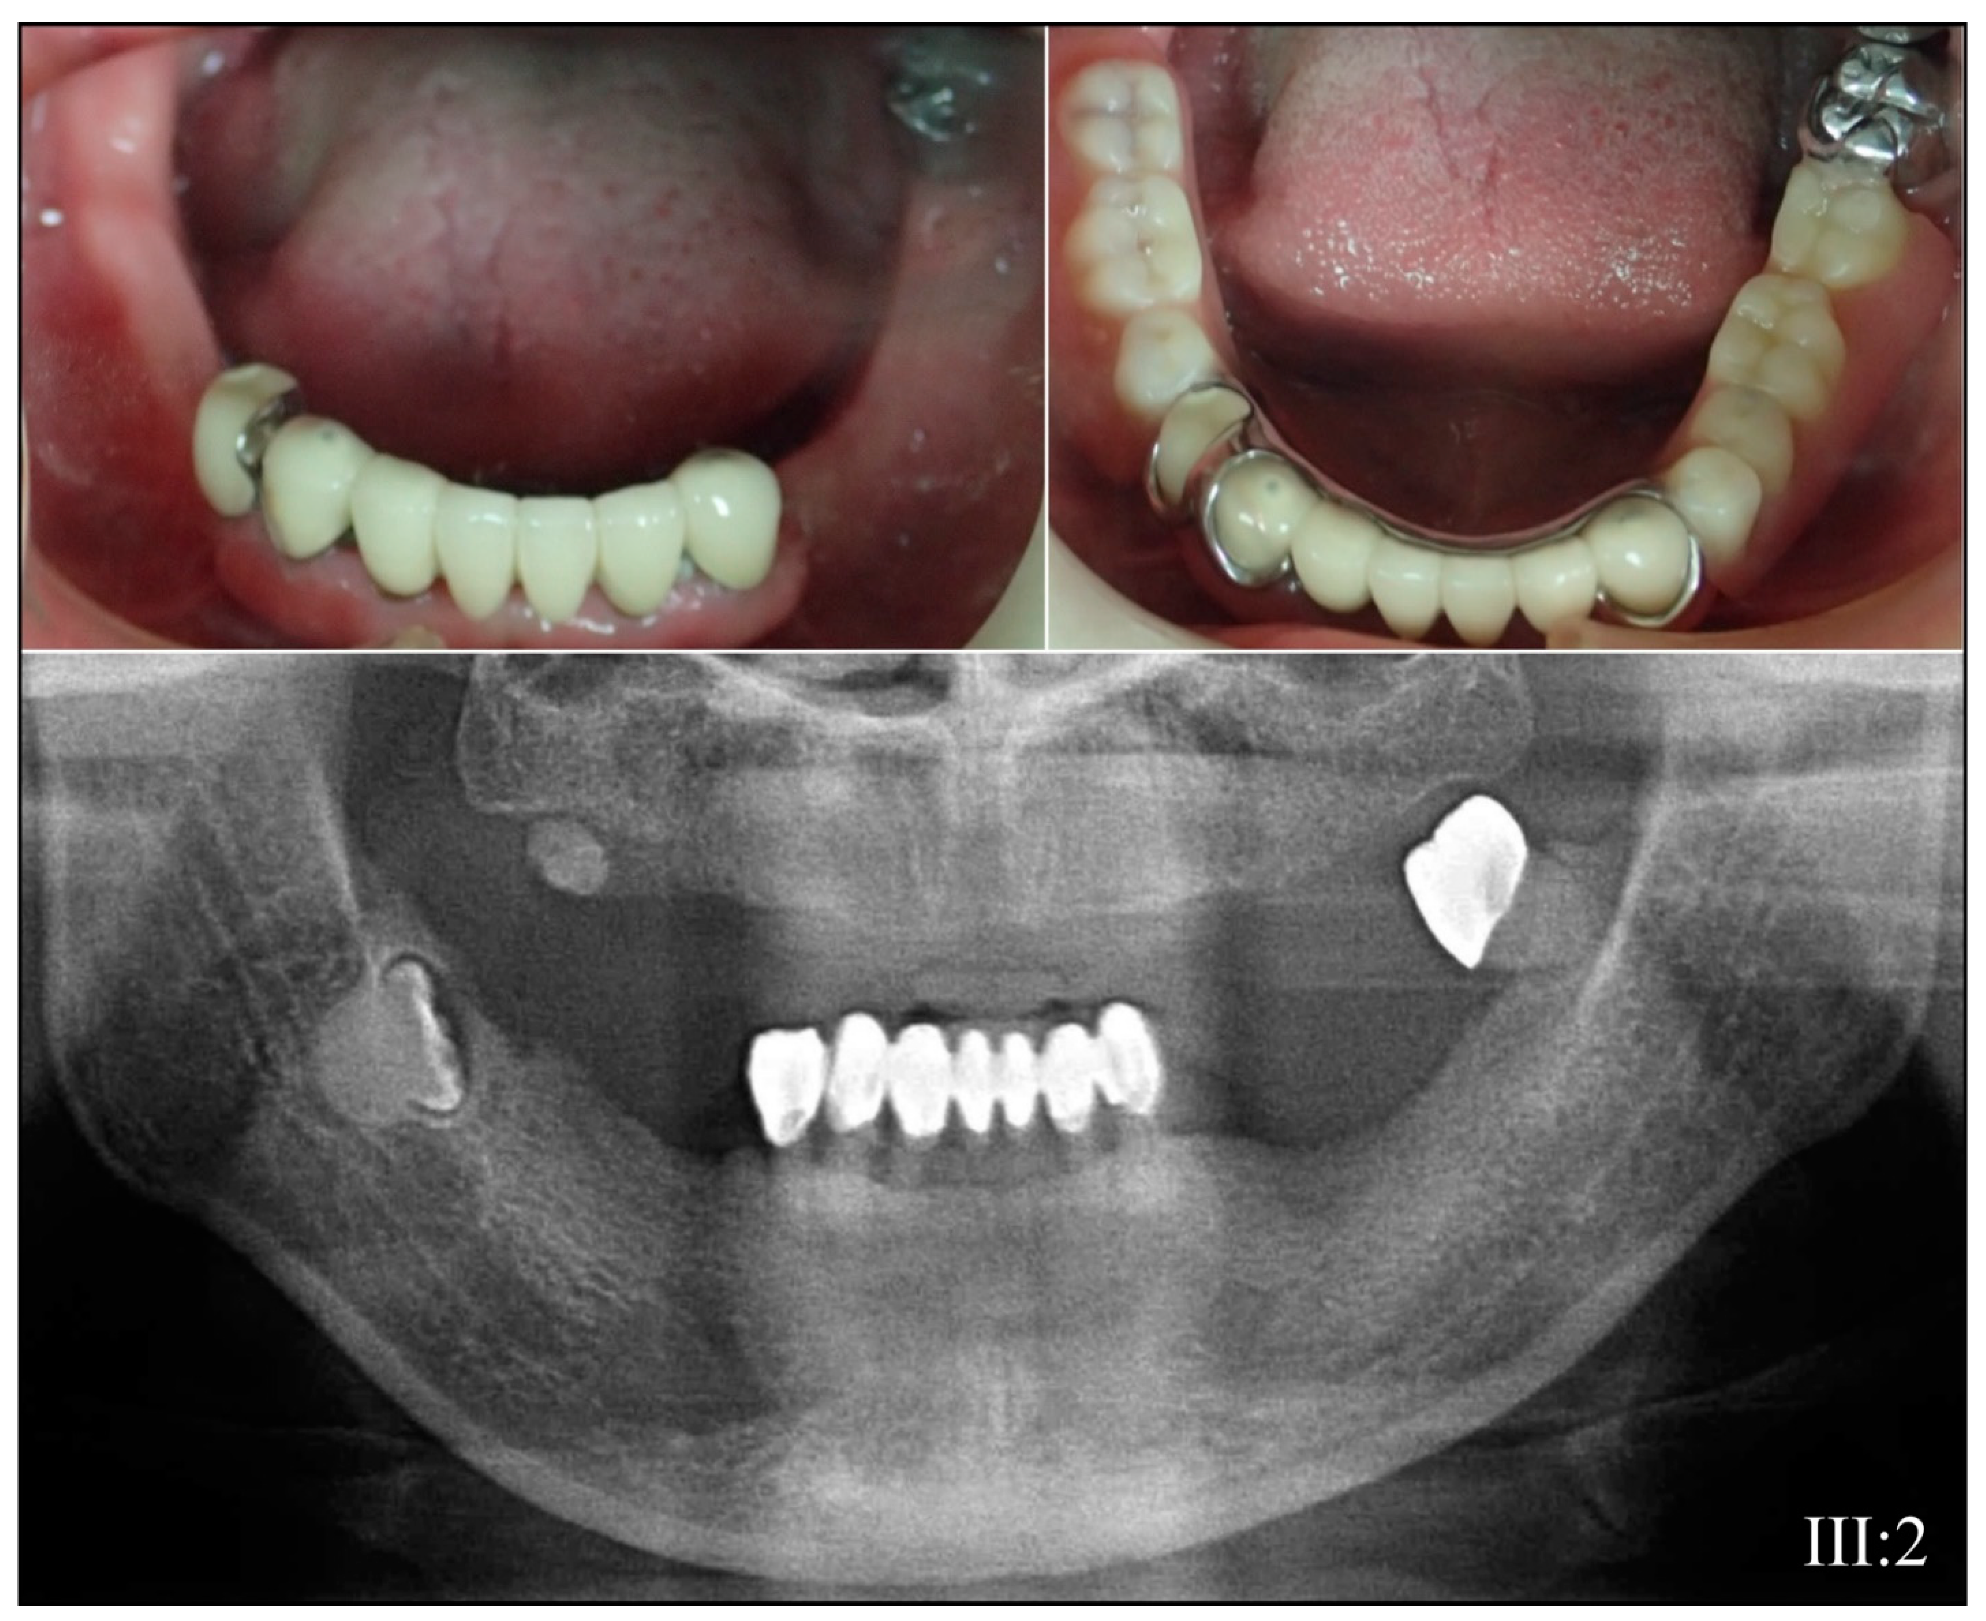

3.2. Four Families with DGI-III: 5′ DSPP Mutations

| 3 | Illumina HiSeq 2500 (WES) | NG_011595.1:g.8578T>C; NM_014208.3:c.53T>C; NP_055023.2:p.(Val18Ala) | Missense | III:2, affected mother: 285.78× IV:2, affected child: 189.42× |